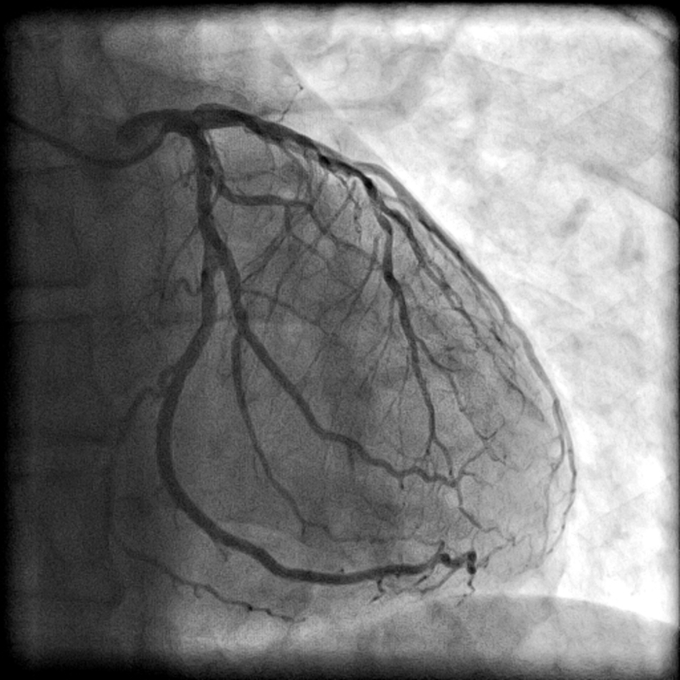

Heart Catheterization With Dye .   for example, a dye can be injected through the catheter that allows your doctor to see the vessels and chambers of your heart using an x.   a coronary angiogram is part of a general group of heart tests and treatments called cardiac catheterization. You may feel some effects when.   during a cardiac cath your health care team may:  once the catheter is in place, your provider will inject contrast dye to visualize the heart and the coronary arteries. A long, thin flexible tube called a catheter is inserted into your.  a coronary angiogram is a dye test used to detect heart problems.

Cardiac catheterization imagine indicating 80 stenosis of the left

A, Coronary catheterization showing (1) RCA, (2) dye spillage Heart Catheterization With Dye    during a cardiac cath your health care team may:  a coronary angiogram is a dye test used to detect heart problems.   a coronary angiogram is part of a general group of heart tests and treatments called cardiac catheterization. A long, thin flexible tube called a catheter is inserted into your.   for example, a dye can be. Heart Catheterization With Dye.